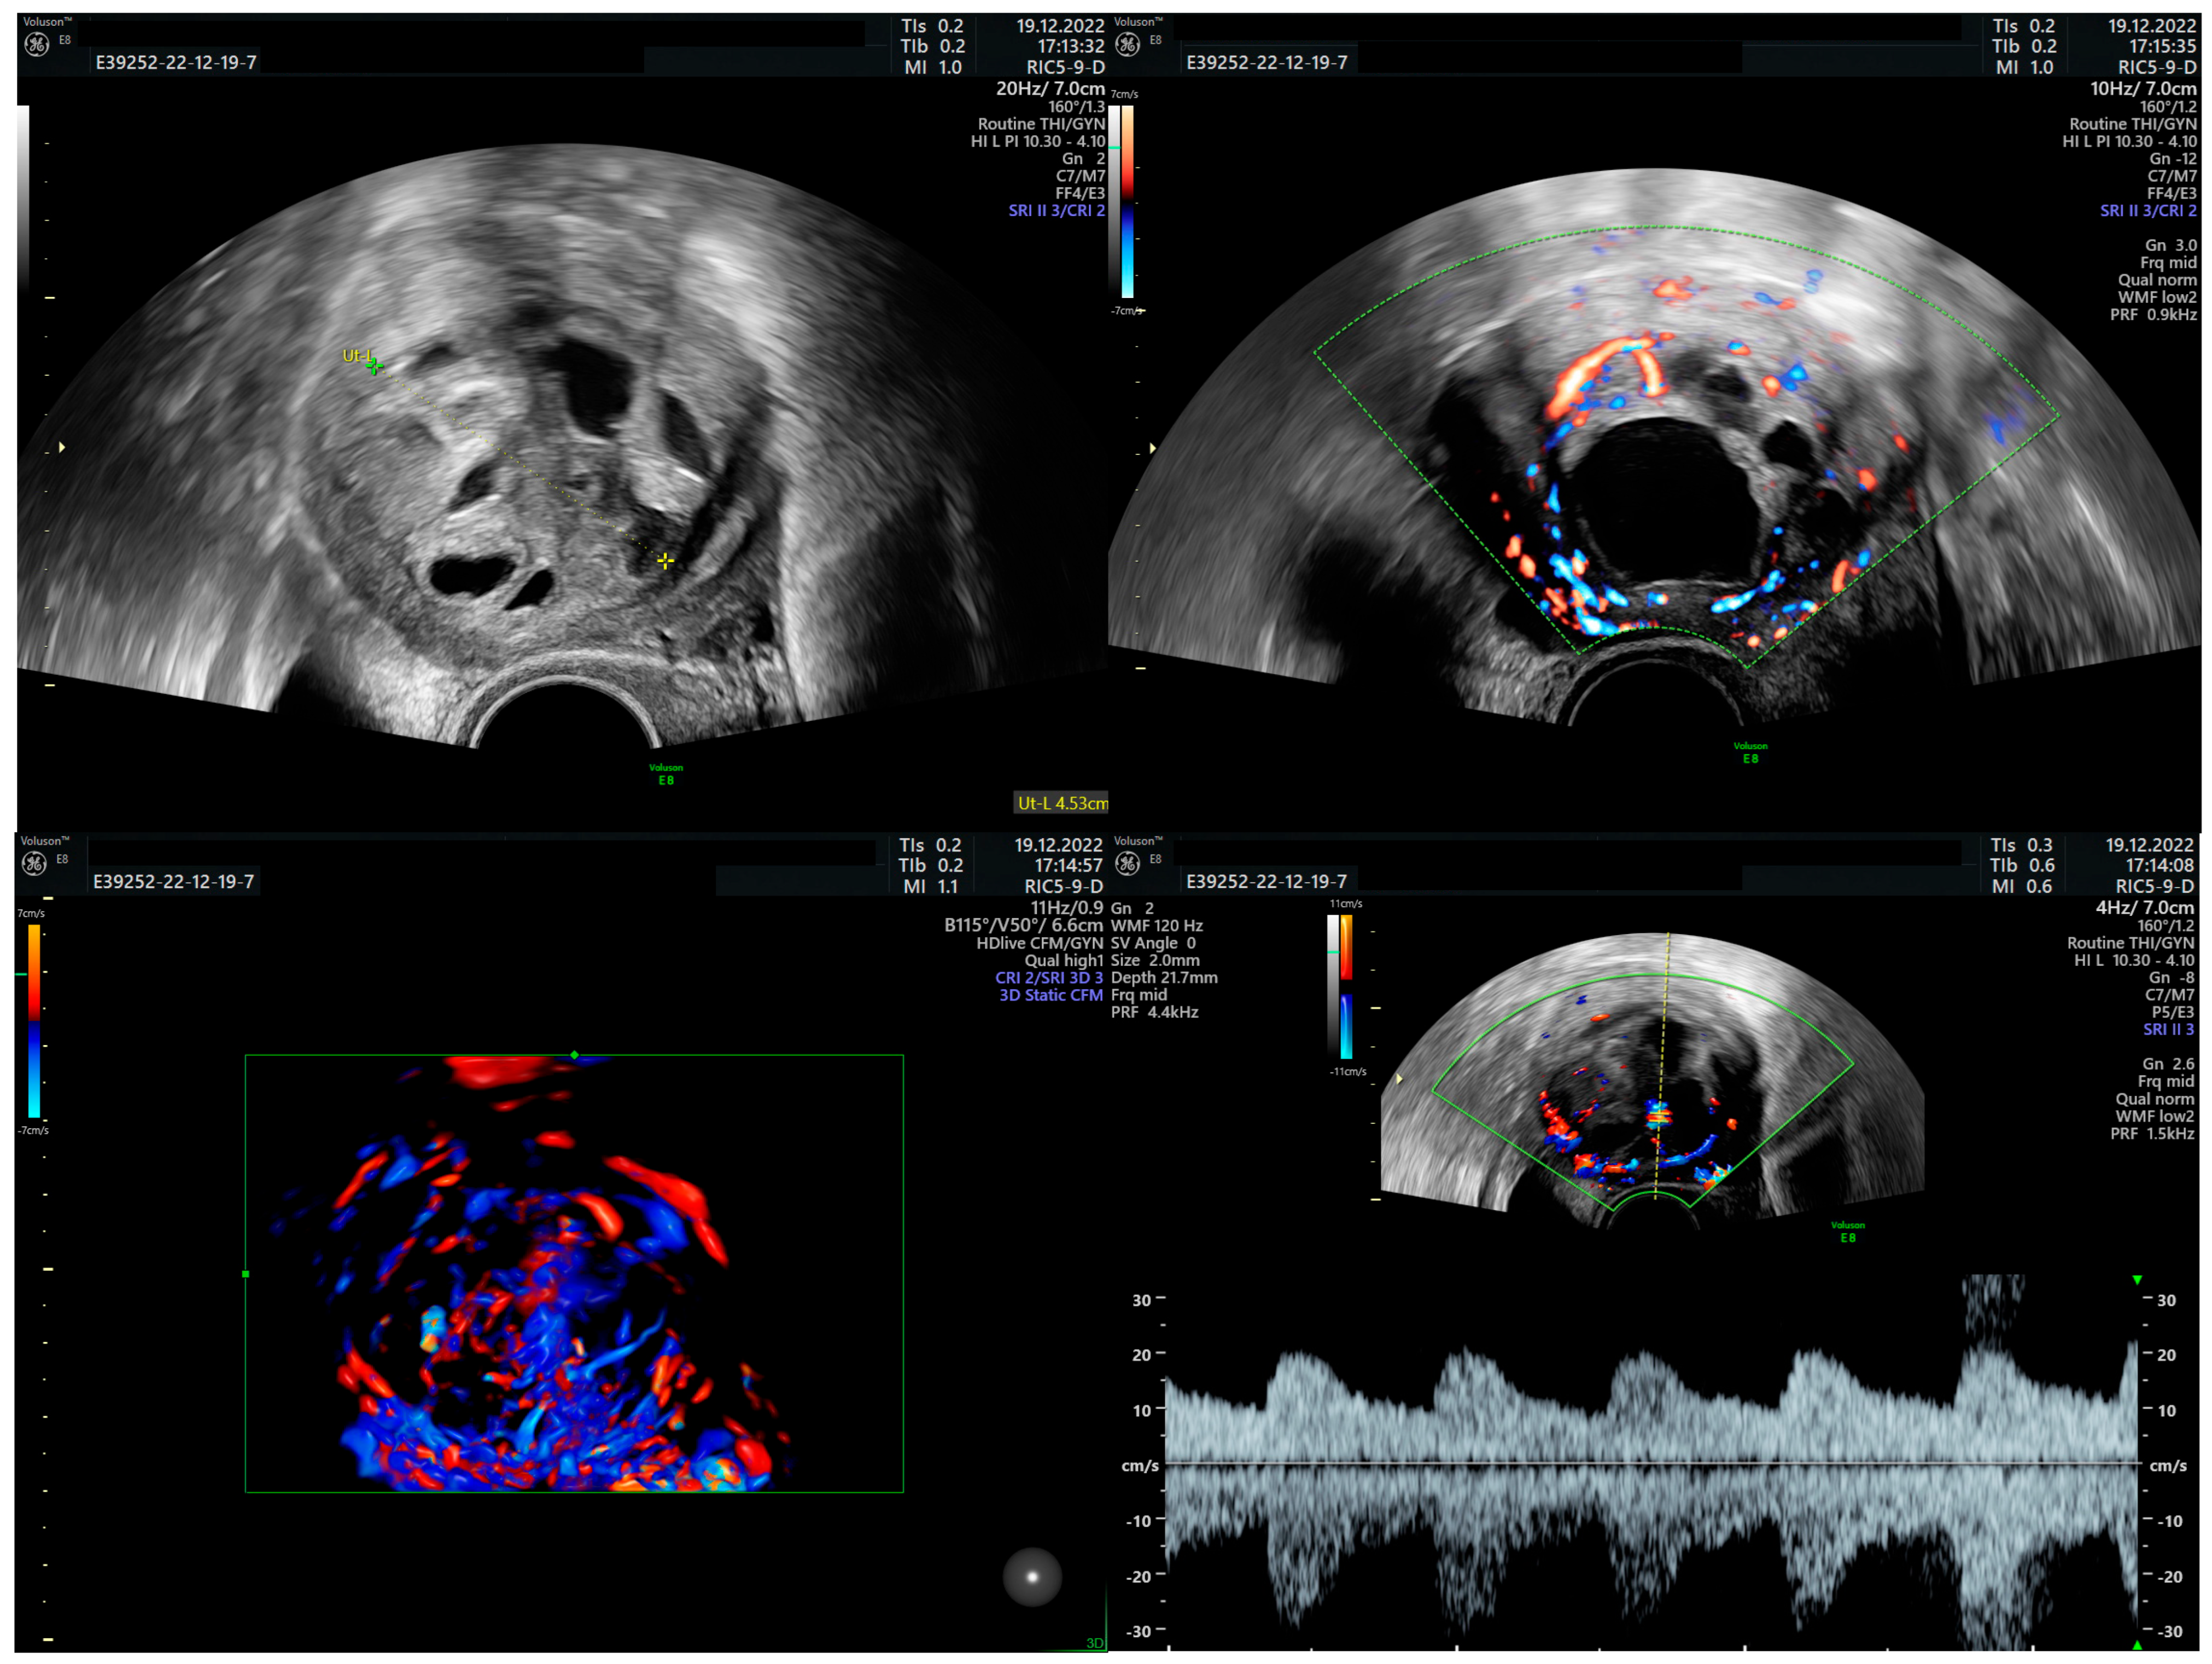

STUMP Swiftly Followed by Large Adenomyoma in a Young Nulliparous Patient

Nemeti, G.; Cruciat, G.; Goidescu, I.G.; Roberta, C.; Ticala, V.M.; Surcel, M.; Goidescu, C.M.; Staicu, A.; Boitor-Borza, D.; Fetica, B.; et al. STUMP Swiftly Followed by Large Adenomyoma in a Young Nulliparous Patient. Diagnostics 2025, 15, 3018. https://doi.org/10.3390/diagnostics15233018